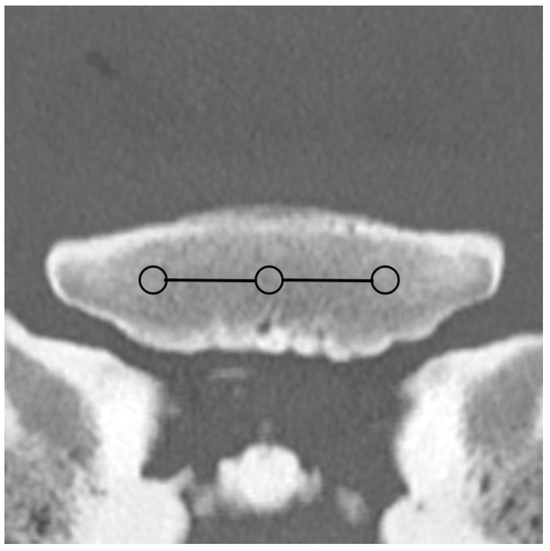

Figure 2. Regions of interest (ROIs; circles) and zones (mean EAN calculated from all ROIs included in an anatomical area; lines) in the palmar/plantar aspect of a front fetlock joint on a transverse monoenergetic image (detector-based spectral computed tomography, Philips) at the mid-level of the proximal sesamoid bones (PSBs): ROIs in the subchondral bone of the medial and lateral metacarpal/metatarsal condyle (palmar/plantar MC/MT zone; continuous line), the dorsal subchondral bone of the medial and lateral PSB (PSB zone; dashed line), and the palmar/plantar FJ zone (continuous rectangular line).

Based on the CT raw data, EAN and ED maps were created from both SSDECT and SBCT images (slice thickness 2 mm), and ROIs were drawn in the virtual monochromatic images (window level 500, window width 2500) using the proprietary software (Raw Data Analysis, CANON Medical and Intellispace Portal 12, Philips Healthcare). Mean EAN/ED values were recorded for each ROI. In total, 29 ROIs and 16 zones were defined for each distal limb. A zone referred to a certain anatomical area, and the mean EAN/ED was calculated from all ROIs included in this area. In the distal aspect of the third metacarpal (MC) and metatarsal (MT) bone, a mid-dorsal image was chosen, and one ROI each was placed in the subchondral bone of the sagittal ridge and the medial and lateral condyle, respectively (dorsal MC/MT zone) (Figure 1). Additionally, a transverse image was chosen at the level of the maximum width of the proximal sesamoid bones (PSB), i.e., at the transition from the distal to the mid-third of the PSBs, and 1 ROI each was placed in the palmar/plantar subchondral bone of the medial and lateral metacarpal/metatarsal condyle (plantar MC/MT zone) and the dorsal subchondral bone of the medial and lateral proximal sesamoid bone (PSB zone) (Figure 2). The mean of all palmar/plantar ROIs in the FJ area (plantar MC/MT and PSB ROIs) represented the palmar/plantar FJ zone (Figure 2). In the first (P1) and second (P2) phalanx, a mid-dorsal image was chosen at the level of the marrow cavity or nutrient foramen, respectively, and in the third phalanx (P3), a dorsal image was chosen parallel to the dorsal surface of the bone at the level of the solar canal. Three ROIs each (medial and lateral fovea, sagittal groove or extensor process) were drawn in the proximal subchondral bone (proximal P1/P2/P3 subchondral zone) and trabecular bone (proximal P1/P2/P3 trabecular zone) distal to the latter in all phalanges (Figure 1 and Figure 3). Larger zones were calculated including all ROIs in the proximal subchondral and trabecular bone of P1, P2 and P3, respectively (proximal epiphyseal P1/P2/P3 zone) (Figure 1 and Figure 3). Moreover, the mean of all dorsal ROIs in the FJ area (distal MC/MT, proximal P1) represented the dorsal FJ zone (Figure 1). A single ROI was also applied to the marrow cavity of P1 (Figure 1). On a mid-dorsal plane of the NB, 3 ROIs were evenly distributed medially, centrally, and laterally within the spongious bone (navicular zone) (Figure 4). All ROIs were of a circular shape with a diameter of 4 mm (smallest ROI possible for both CT units) except for the circular ROI in the marrow cavity of P1, the diameter of which was adapted to the size of the marrow cavity.